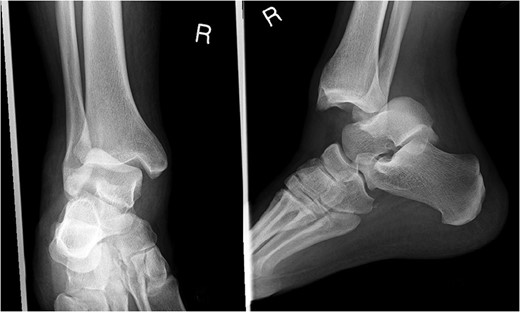

A 30-year-old male patient presented to Emergency Department (ED) following a run over injury. The patient described the mechanism of injury as moving his body over his run over foot. On clinical examination, there was obvious deformity and swelling of the right ankle. Dorsalis pedis pulse was felt but weak compared to the contralateral side with a capillary refill time under 3 s. The posterior tibial artery could not be palpated because of the deformity. X-rays showed posterior ankle dislocation without associated fractures (Fig. 1). Urgent reduction of the dislocation was done under sedation in ED. The knee was first flexed to relax the tendon Achilles then longitudinal traction with gentle forward force applied to the heel with immediate reduction of the deformity achieved. The foot was reassessed for vascular status. Triphasic pulse in both drosalis pedis and posterior tibial artery was detected with hand held Doppler. Ankle was immobilized in posterior below knee back slab to accommodate for swelling and check x-rays confirmed reduction of the ankle joint (Fig. 2). CT scan was done afterwards to define any subtle incongruity or osteochondral fragments entrapped in the joint. CT did not show any associated fractures and showed congruent reduction of the ankle joint (Fig. 3). Patient was mobilized touch weight bearing for first 2 weeks. The back slab was changed for weight bearing short leg cast and progressive weight bearing was allowed for the following 4 weeks. At 6 weeks follow up, plaster was removed and on examination patient still had moderate tenderness over the medial joint line and deltoid ligament area. Also, patient had limited range of plantar and dorsal flexion. Referral for physiotherapy was done for start of functional rehabilitation and range of motion exercises and in mean time MRI was done to delineate extent of ligamentous injury. MRI showed bone bruising of the lateral malleolus, medial malleolus and lateral talus (Fig. 4). The anterior talufibular ligament (ATFL), calcaneofibular ligament (CFL), posterior talofibular ligament (PTFL) and deltoid ligaments were sprained but intact. At 12 weeks follow up, patient could walk normally without any symptoms of instability and achieved 20° of both plantar and dorsal flexion. At 16 weeks, patient achieved full range of motion of ankle and was able to return to work. At 24 weeks follow up patient was able to resume his sport activates as preinjury level.

T2 MRI images showing high signal in medial malleolus, lateral malleolus and talus signifying bone bruise.